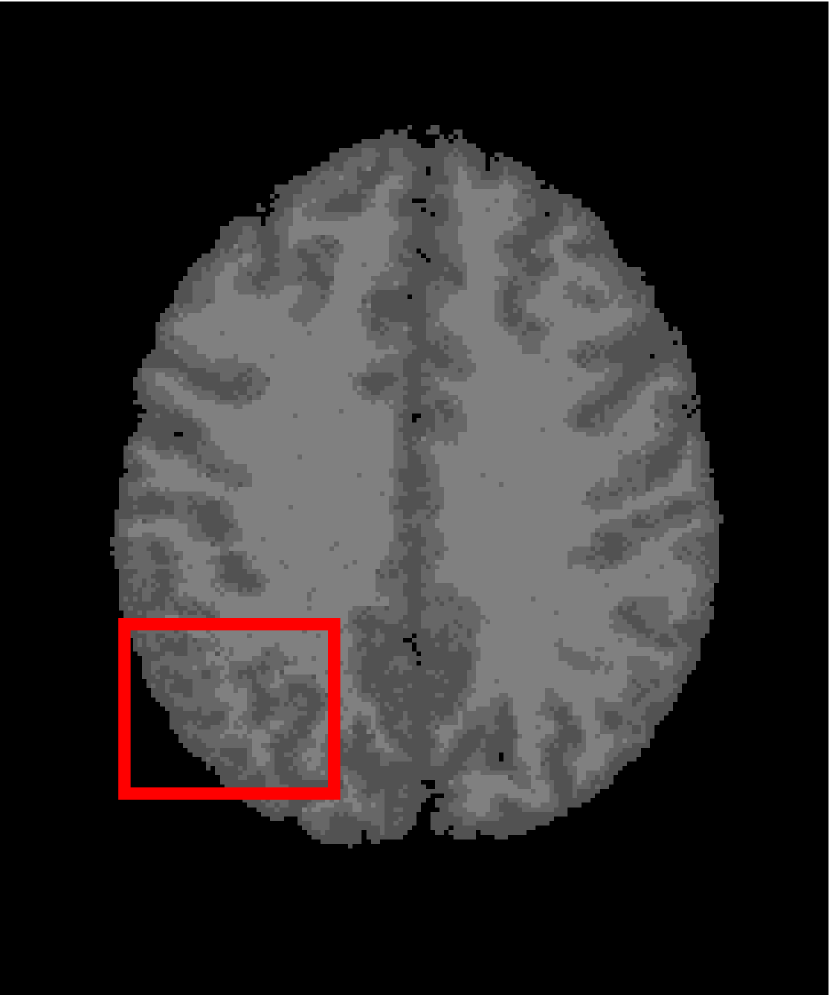

In the second experiments, we segment two medical images coming from a simulated brain database (BrianWeb): http://www.bic.mni.mcgill.ca/brainweb/. The two images are generated by T1 modality with slice thickness of 1mm resolution, 9% noise and 20% intensity non-uniformity. Here, the two images are represented two slices in the axial plane with the sequence of 100 and 110. Moreover, there are golden standard segmentations in the dataset. We set the numbers of clusters to 4. The visual comparisons are illustrated in Figs. 6 and 7.

Figure 6: Segmentation results for the first medical image. From (a) to (l): ground truth, noisy image and results of FCM_S1, FCM_S2, FGFCM, FLICM, KWFLICM, ARKFCM, FRFCM, WFCM, DSFCM_N, and LRFCM.

By focusing on the marked red square in Figs. 6 and 7, we easily find that FCM_S1, FCM_S2, FGFCM and ARKFCM are sensitive to noise. FLICM and KWFLICM are vulnerable to severe intensity inhomogeneity. FRFCM brings overly smooth results due to the use of gray level histograms. WFCM and DSFCM_N cause several contours to change. However, LRFCM acquires clear contours and suppresses noise adequately. Moreover, we find that the segmentation result of LRFCM is closer to ground truth.